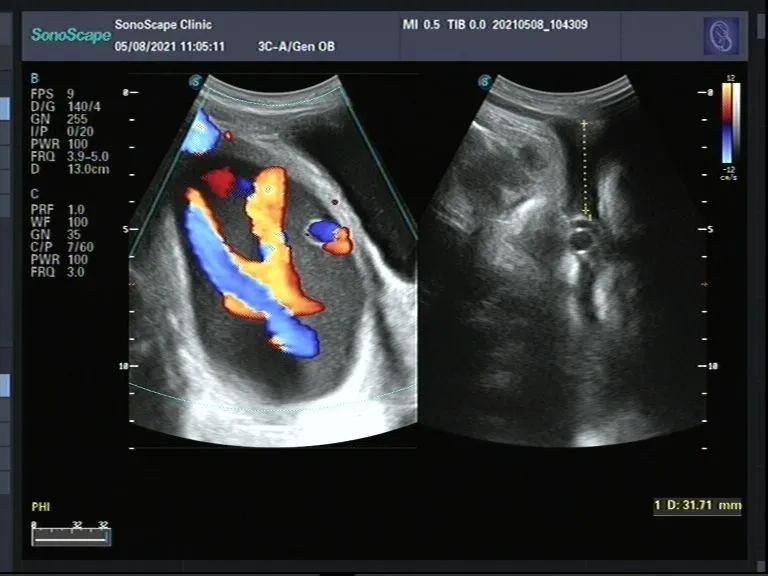

当日上午,援藏医疗队与昂仁县人民医院全体医护人员正在多功能厅通过远程连线参加淄博市中心医院组织的手卫生活动。援藏医疗队员修宇突然接到同事电话,有位急症孕妇需要B超会诊。修宇急速赶到,第一时间明确诊断,遂即通知队员孙丰涛:“第三胎经产妇,孕36周,臀位伴脐带脱垂,情况危急......”